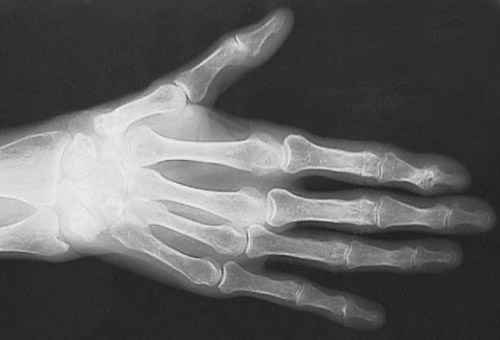

This radiographic view of the hand demonstrate changes of osteoarthritis with loss of the joint space of the distal interphalangeal joint of the index finger on the right hand.